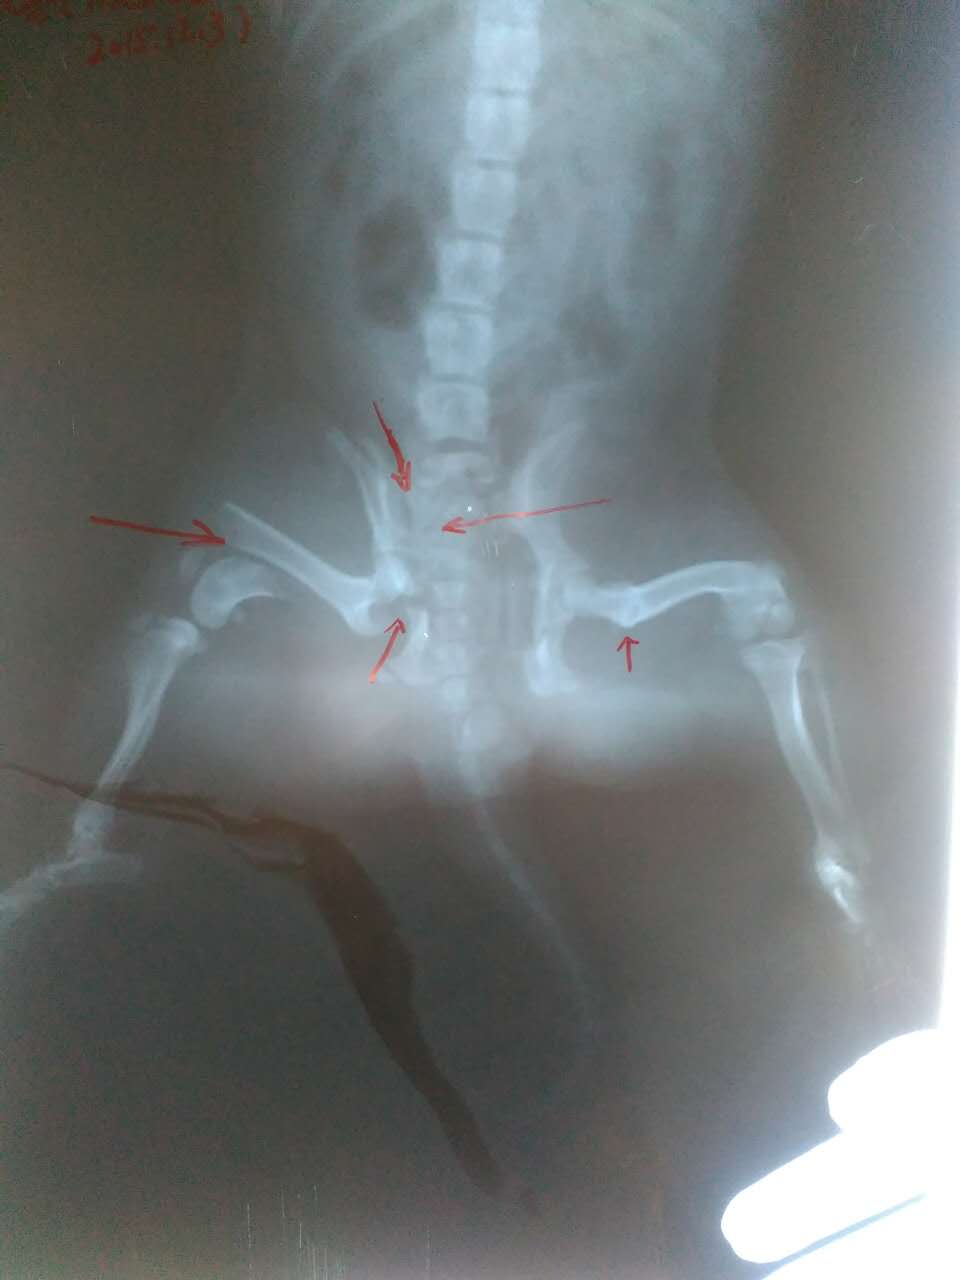

可愛斗牛犬胯骨股骨嚴重骨折,術后痊愈!